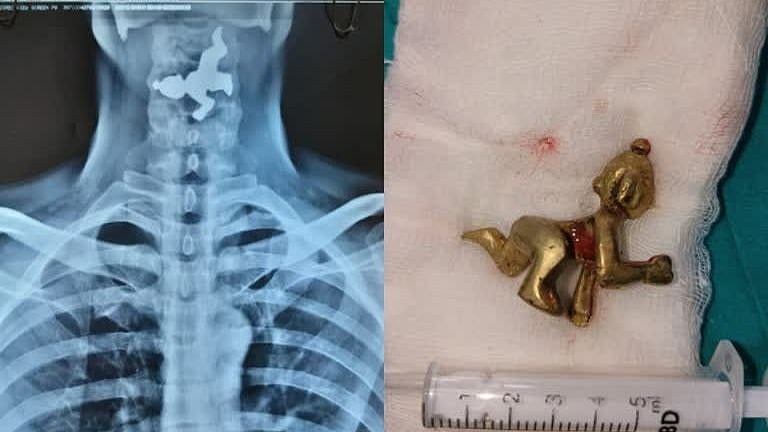

கர்நாடக மாநிலம் பெலகவி மாவட்டத்தில், 45 வயது மிக்க நபர் ஒருவர் தனக்கு தொண்டை வலி இருப்பதோடு மூச்சு விடுவதில் சிரமம் இருப்பதாக கூறி தனியார் மருத்துவமனையை அணுகினார். எனவே அங்குள்ள மருத்துவர்கள் அவருக்கு X-Ray எடுத்து பரிசோதனை செய்தனர். X-Ray ரிப்போர்ட்டை பார்த்த மருத்துவர்கள் அதிர்ச்சியடைந்தனர்.

அதில், அவரது தொண்டையிலுள்ள உணவு குழாயில் இரும்பு வடிவிலான பொருள் ஒன்று சிக்கியுள்ளது தெரிந்தது. பின்னர் இது குறித்து அவரிடம் விசாரித்த போது, தான் எதையும் உட்கோள்ளவில்லை என்று தெரிவித்தார். தொடர்ந்து அவரிடம் கேட்கையில், தான் வழக்கமாக அருகிலிருக்கும் ஒரு கோயிலில் நீராடி, அந்த நீரை பருகுவதாக தெரிவித்தார்.

இதனையடுத்து, அவருக்கு ENDOSCOPY என்ற சிகிச்சை மூலம் தொண்டையில் சிக்கியிருந்த பொருளை தொண்டை வழியே வெளியே எடுத்தனர். இது குறித்து மருத்துவர்கள் கூறுகையில், 45 வயது மதிக்கத்தக்க நபர் ஒருவர் தனக்கு மூச்சு விடுவதில் சிரமமாக இருப்பதாக அணுகினார்.

அவரை பரிசோதனை செய்ததில், தொண்டையில் பொருள் இருப்பது கண்டுபிடிக்கப்பட்டு, சிகிச்சை மூலம் வெளியே எடுக்கப்பட்டது. இந்த சிகிச்சையின்போது உணவுக் குழாயில் சிலையின் இடது கால் சிக்கிக் கொண்டதால் எங்களுக்கு மிகவும் கடினமாகவும் சவாலாக இருந்தது. எனவே எதை சாப்பிட வேண்டுமென்றால் பார்த்து சாப்பிடுங்கள், பருகுங்கள்" என்றனர்.